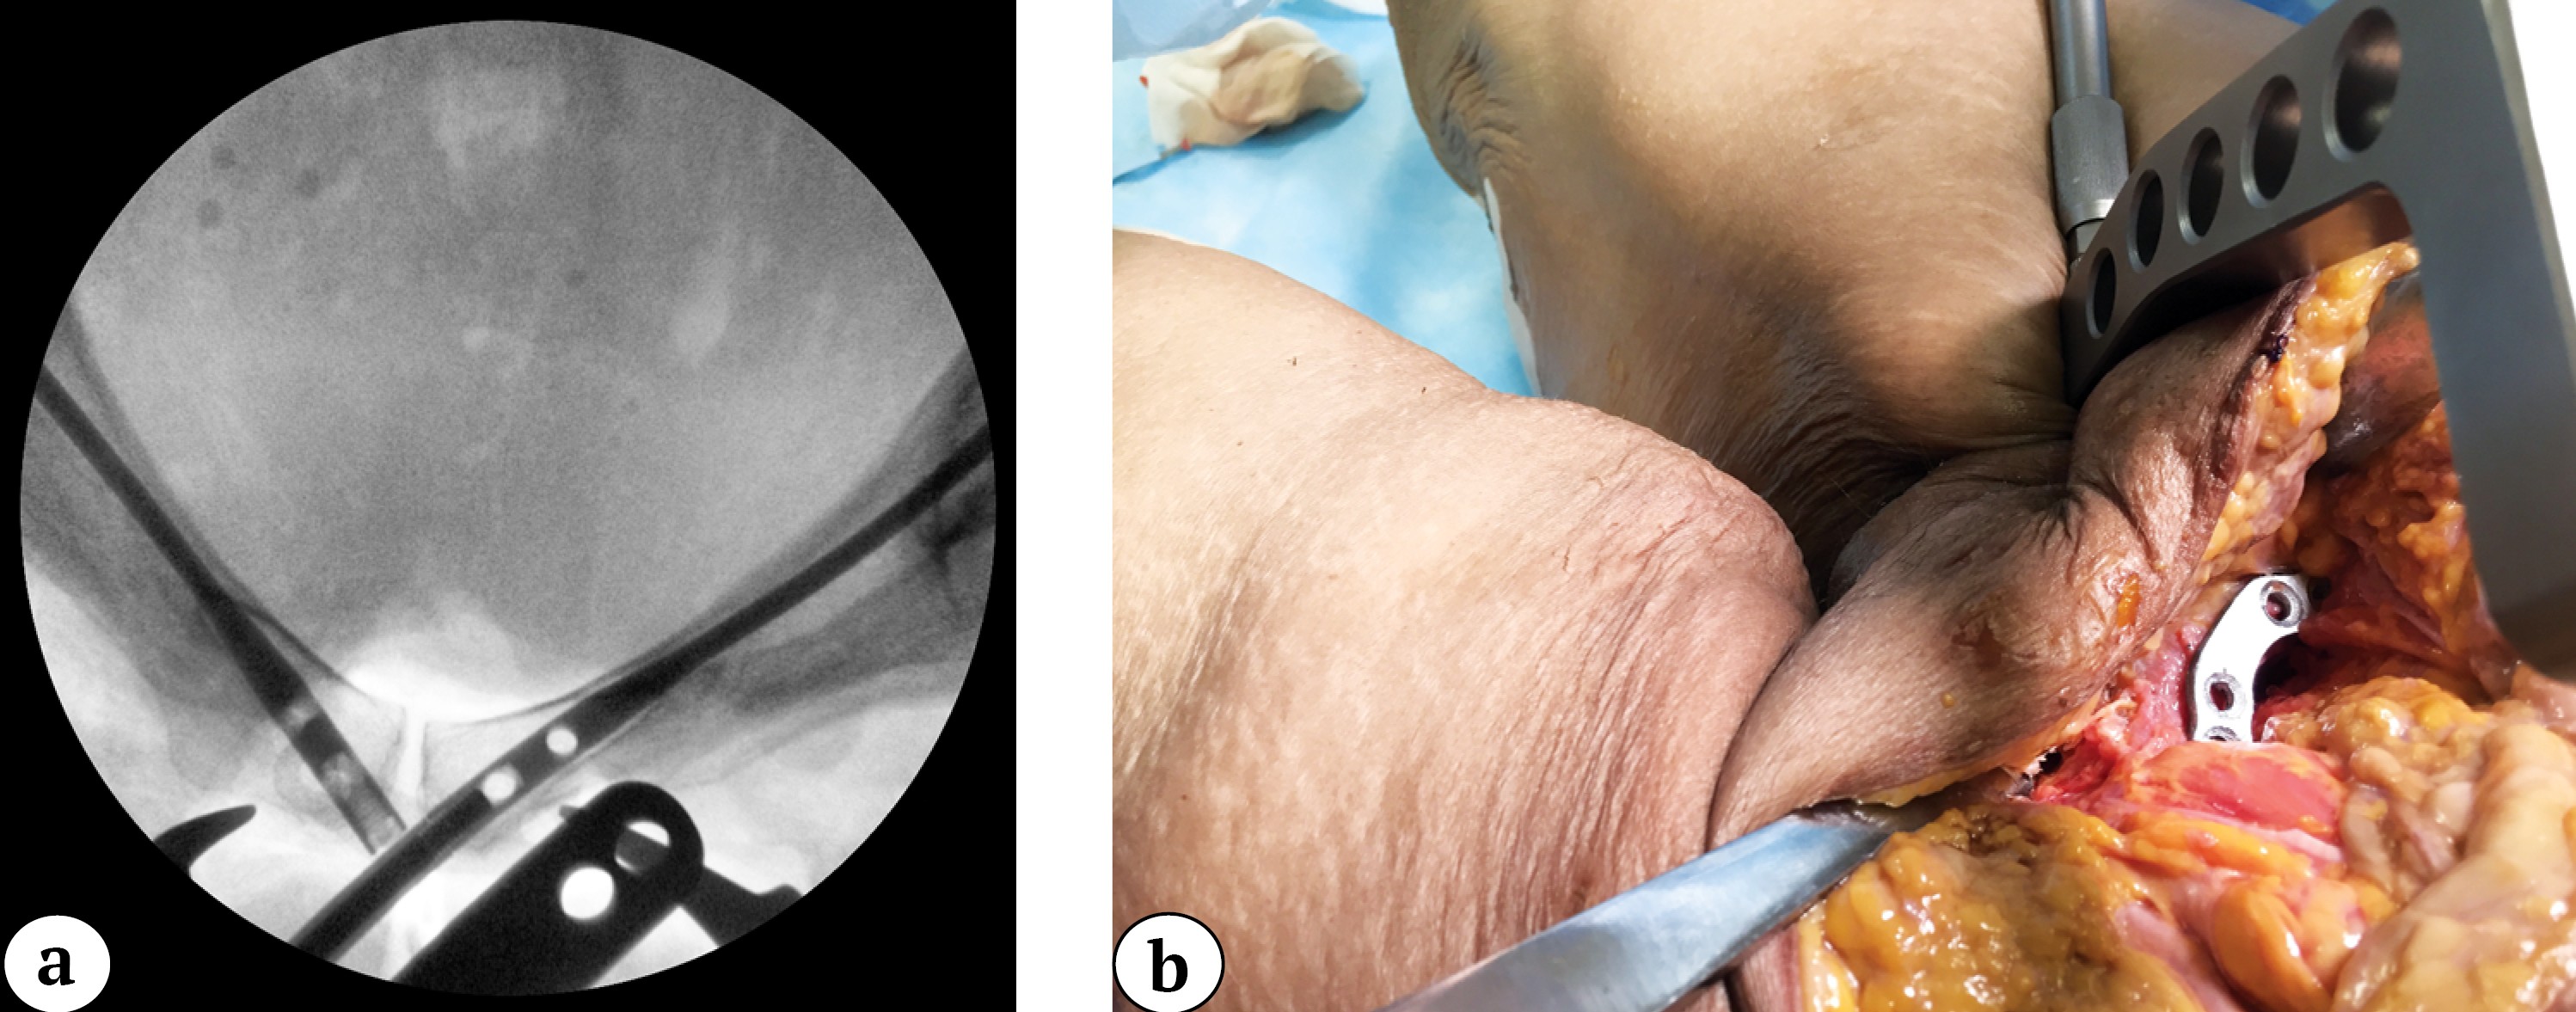

To prevent displacement, the plate was temporarily fixed with a 2-mm wire through the technical hole. A drill sleeve was inserted through the guide handle and aligned with the hole in the plate closest to the symphysis (Figure 4).

Figure 4. Intraoperative outlet view of the pelvis with the guide cannula aligned for nail locking through the plate hole (a); nail locking via the plate hole (b)

If necessary, the nail was slightly adjusted in a retrograde or antegrade direction to achieve precise alignment of the drill sleeve with the plate hole. The nail was then locked with two 3.5-mm cortical screws through the plate holes (Figure 5). The guide was removed and attached to the second nail (the ends of the nails usually protrude 1-2 mm from the entry points and are easily palpable). The optimal angle of the guide for subsequent nail locking was achieved by rotating it around the nail axis under C-arm control.

Figure 5. Intraoperative obturator-outlet view of the pelvis during locking of the nail with a 3.5-mm screw through the plate hole (a); intraoperative photograph of the surgical site showing interlocking of the second nail through the plate hole (b)